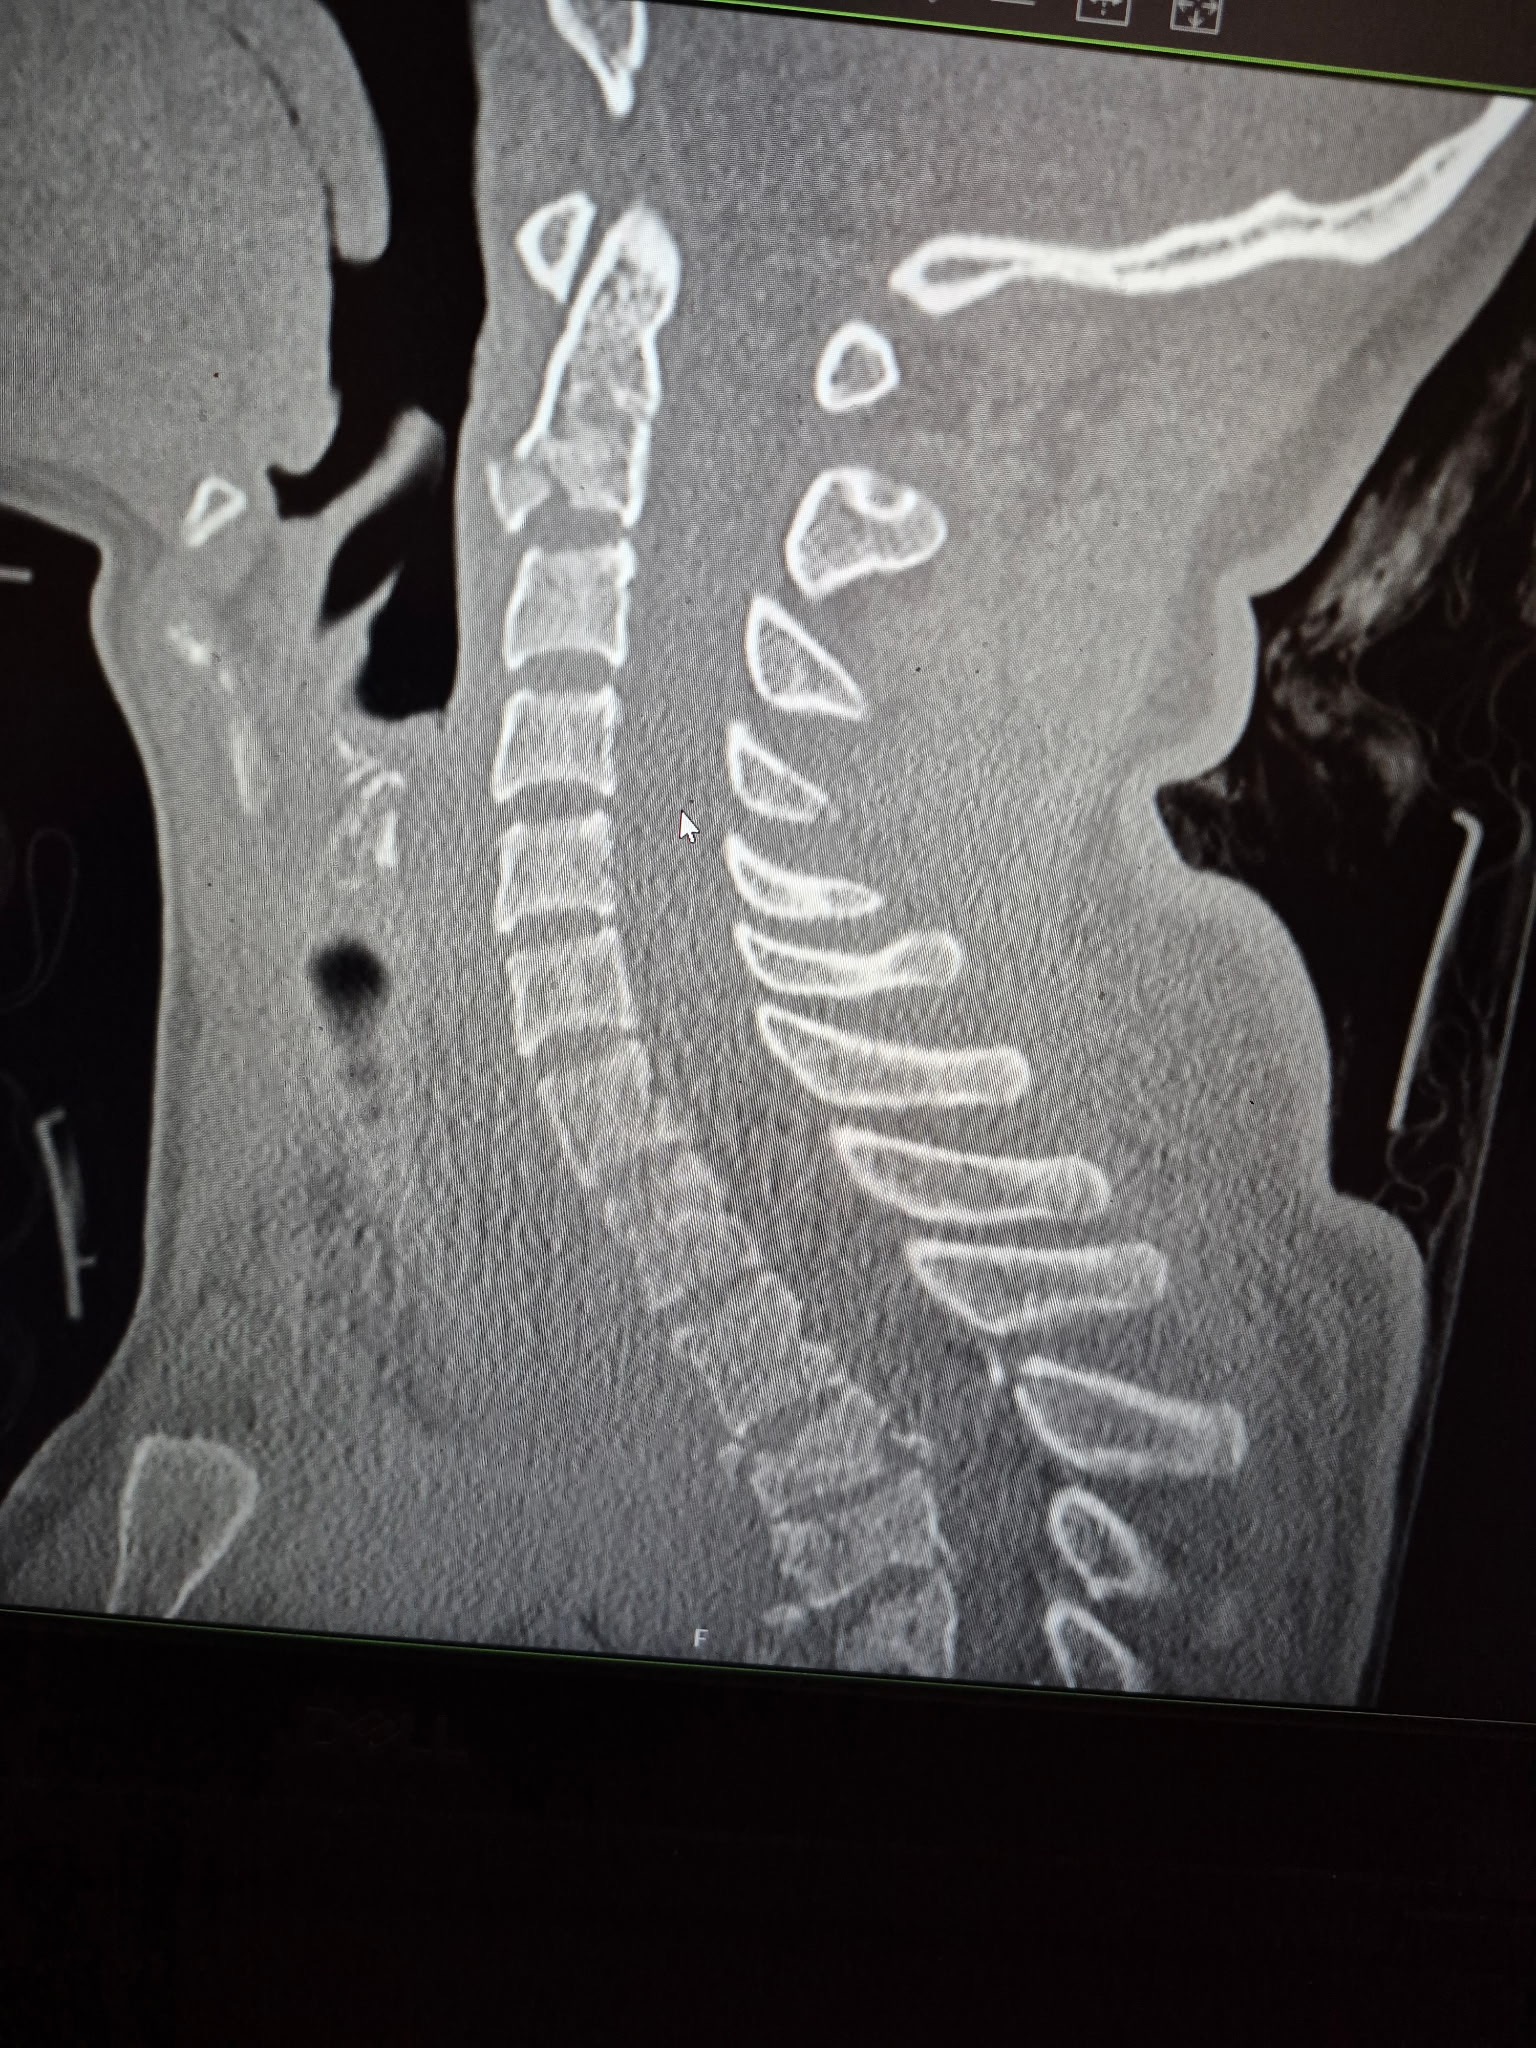

He had an epidural hematoma which required a craniotomy, a broken sternum, around 5 broken ribs, multiple broken cervical and thoracic vertebrae requiring a T1-T8 spinal fusion, and a long hospital stay.